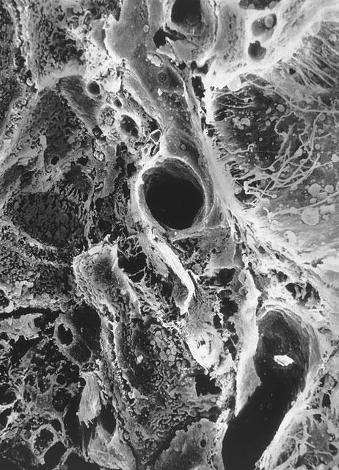

Исследователи не скрывают — чтобы заглянуть в глубины мозга: изучить при помощи микроскопов и других исследовательских приборов, что, собственно, происходит внутри нейронной сети в процессе обработки информации и обучения. Далее, когда они получат схему работы сети, которая самоорганизовалась и научилась что-то делать, можно будет создать математическую модель, которую, в свою очередь, зашить в микрочип. Он станет самоорганизующейся системой обработки информации, своего рода искусственным интеллектом. Ни больше ни меньше.